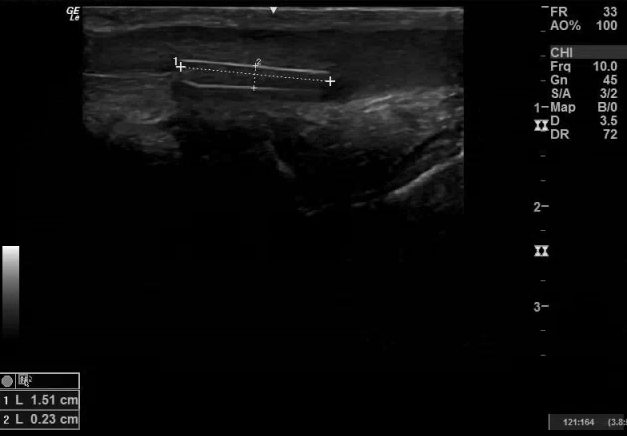

57 yo male with PMH of schizoaffective disorder presented from an inpatient psychiatric unit to the ED complaining of a foreign body (FB) in his urethra. He has a history of inserting FBs into his ears. The patient reported that he inserted a plastic fork handle into his urethra about one week ago and was now straining to void, although still passing urine. On physical exam, there was a FB palpable under the skin on the ventral side of the penis. Point-of-care ultrasound (POCUS) was performed:

After the presence of an FB was confirmed on POCUS, urology was consulted and was able to directly visualize and extract two plastic shards from the distal urethra. Unsure if there was still a deeper retained FB, urology then asked for a repeat POCUS, which demonstrated one more FB in the more proximal urethra:

The surfaces of FBs always appear hyperechoic (bright) on ultrasound. If the FB has been retained for a longer time (>24 hr), surrounding inflammation can develop and appears as a hypoechoic (darker) ring around the FB. Depending on the material of the FB, it may create artifacts such as posterior shadowing or reverberation. When looking for an FB in a finger or toe, utilize a water bath for better visualization. Open wounds can be covered with a Tegaderm. Ultrasound can also be used to actively guide foreign body retrieval with in-plane needling.